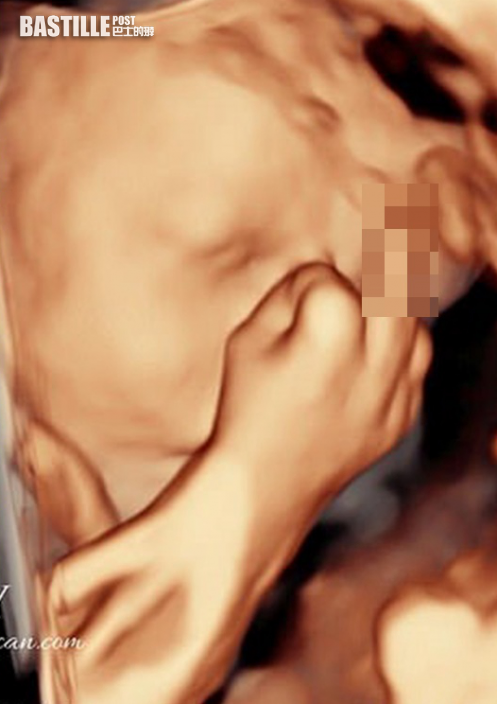

英婦30周做超聲波產檢 見胎兒「擺出驚人手勢」

英國柴郡一名24歲孕婦進行超聲波檢查時,驚見腹中胎兒舉起中指。爸爸接受訪問表示,胎兒的舉動讓他哭笑不得,於是把照片分享給親朋好友,並熱切期待BB的出生。

24歲孕婦杰絲做產檢時,看見兒子向他們舉起中指。網圖

23歲未婚夫大衛(David Lewis)當時和懷有30周身孕的杰絲強森一起觀察寶寶動態,并形容兒子開頭似乎有些害羞地把臉遮起來,有時還做出類似打哈欠的動作,在結束產檢5分鐘前,他們發現兒子作出不雅的手勢「他對我們舉中指,就好像在說『看夠照片了,別打擾我』。」杰絲表示,舉中指動作沒有維持太久,「等到他出生,我一定會提起這件事取笑他。」